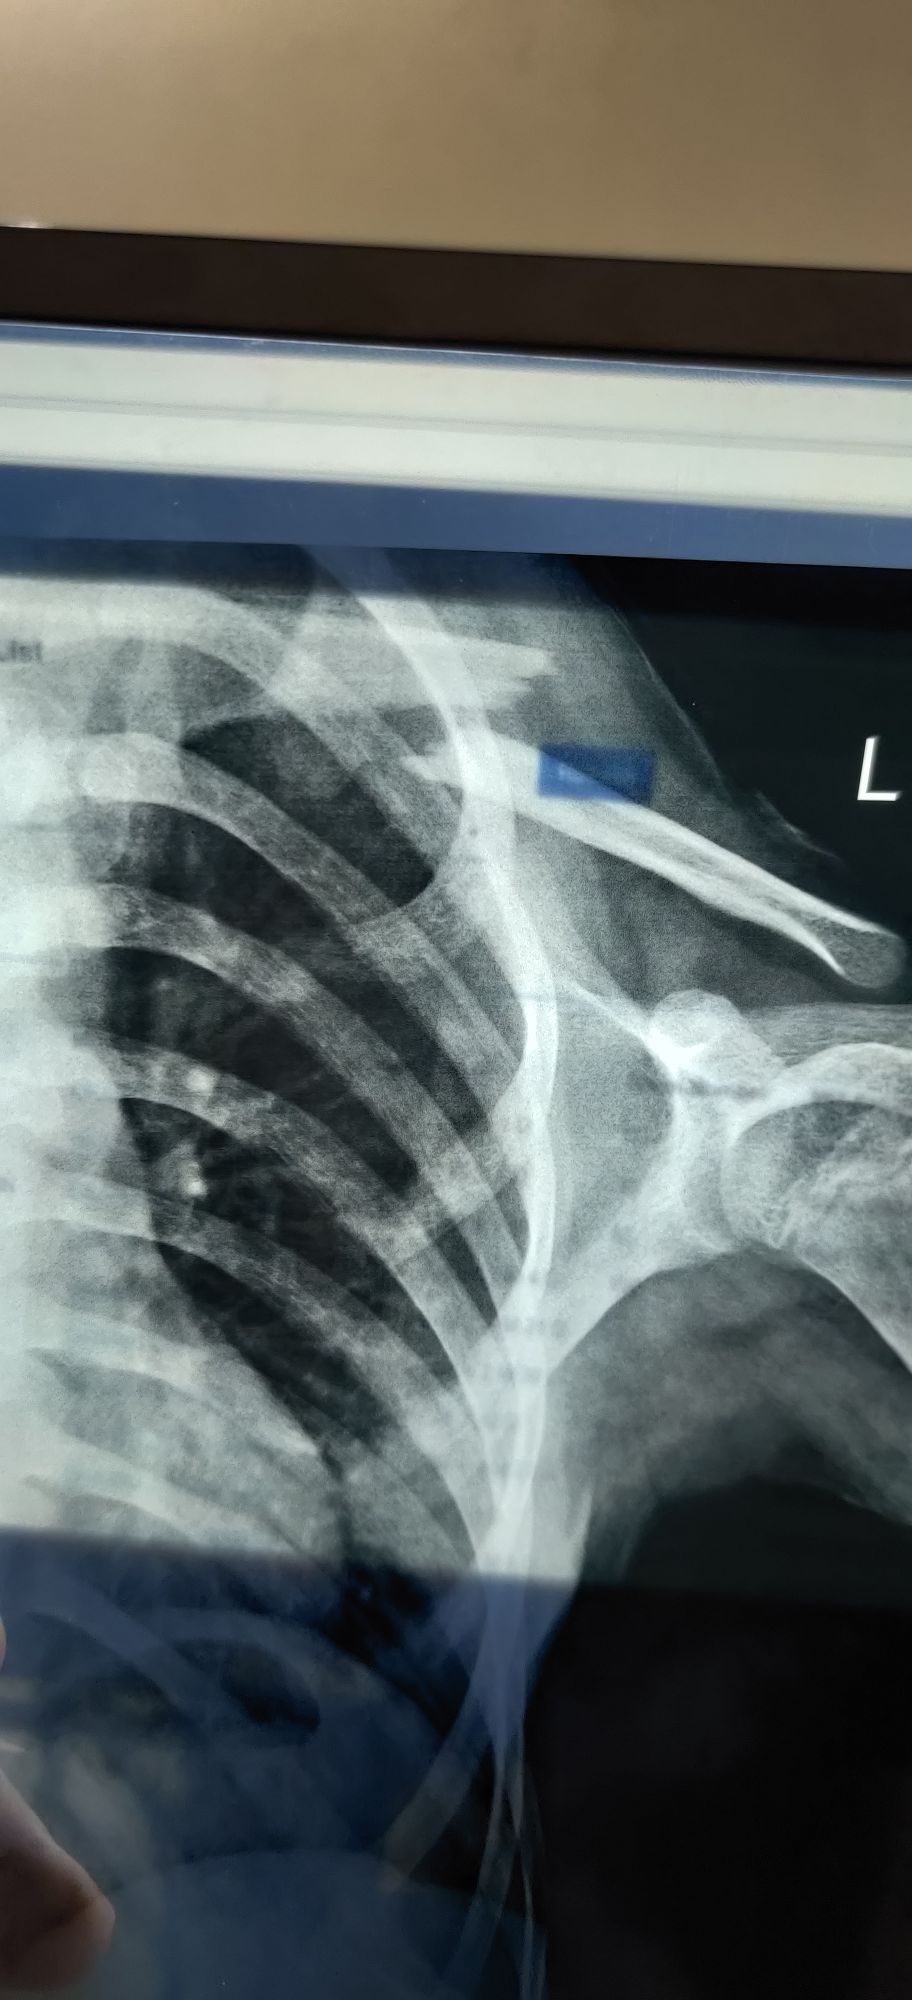

L Clavicle Fracture

Ortho

Clavicle

Fractured